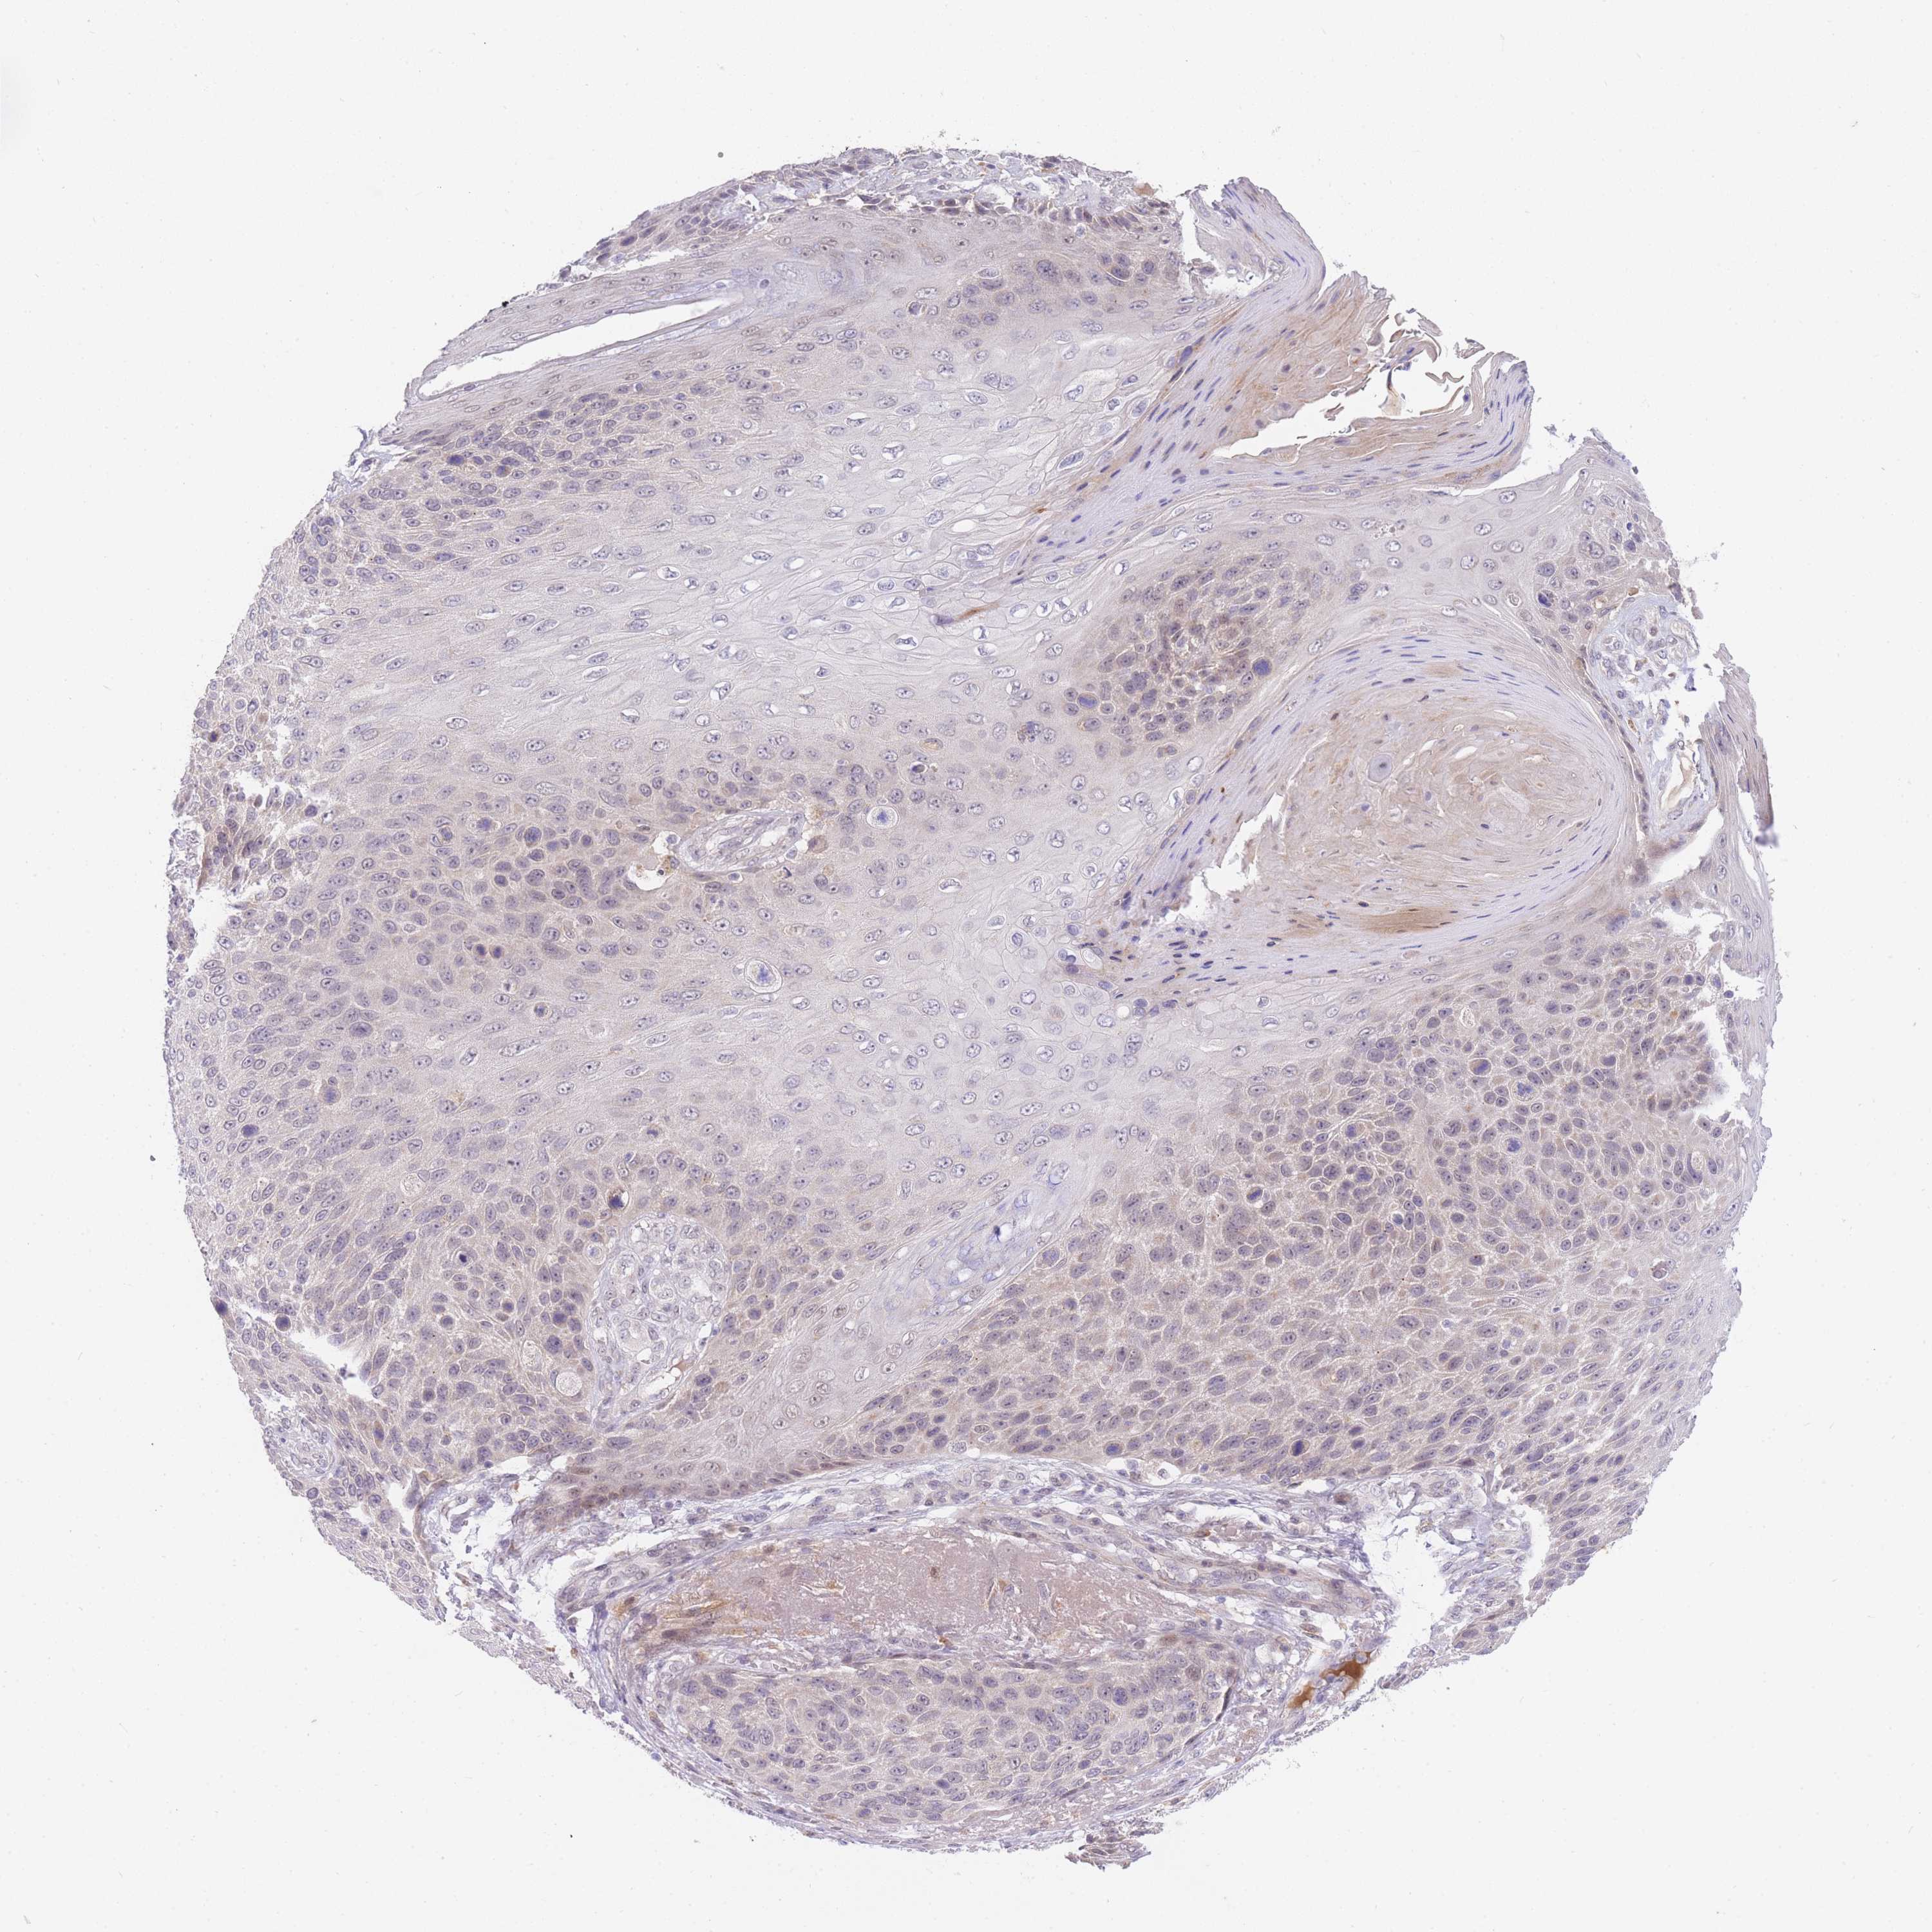

Basal cell and squamous cell cancer

SKIN CANCER - Protein expressioni

A mouse-over function shows sample information and annotation data. Click on an image to view it in a full screen mode. Samples can be filtered based on level of antibody staining by selecting one or several of the following categories: high, medium, low and not detected. The assay and annotation is described here.

Antibody stainingi

Antibody staining in the annotated cell types in the current human tissue is reported as not detected, low, medium, or high, based on conventional immunohistochemistry profiling in selected tissues. This score is based on the combination of the staining intensity and fraction of stained cells.

Each image is clickable and will lead to virtual microscopy that enables deeper exploration of all samples and also displays staining intensity scores, fraction scores and subcellular localization as well as patient and tissue information for each sample.

Antibody HPA049982

Staining

High

Medium

Low

Not detected

Intensity

Strong

Moderate

Weak

Negative

Quantity

>75%

75%-25%

<25%

None

Location

Nuclear

Cytoplasmic/membranous

Cytoplasmic/membranous,nuclear

Basal cell carcinoma

Squamous cell carcinoma, NOS

Squamous cell carcinoma, metastatic, NOS